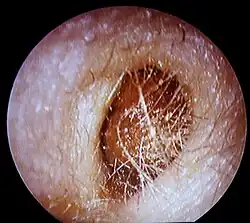

Das Cerumen kann den Gehörgang, unter anderem bei Überproduktion, völlig verschließen (Ohrenschmalzpfropf, Ceruminalpfropf, Cerumen obturans) und plötzliche Schwerhörigkeit bewirken.[14] Der Pfropf muss vom Hausarzt oder Hals-Nasen-Ohren-Arzt mittels eines Ohrlöffels oder per Absaugung entfernt oder notfalls mit warmem Wasser herausgespült werden. Ist dies nicht möglich, weil der Pfropf zu fest sitzt, kann ein Arzt mit einigen Tropfen Wasserstoffperoxid in einer Konzentration von 3 % den Pfropf anlösen,[15][16] um ihn dann anschließend ausspülen zu können.[17][18]